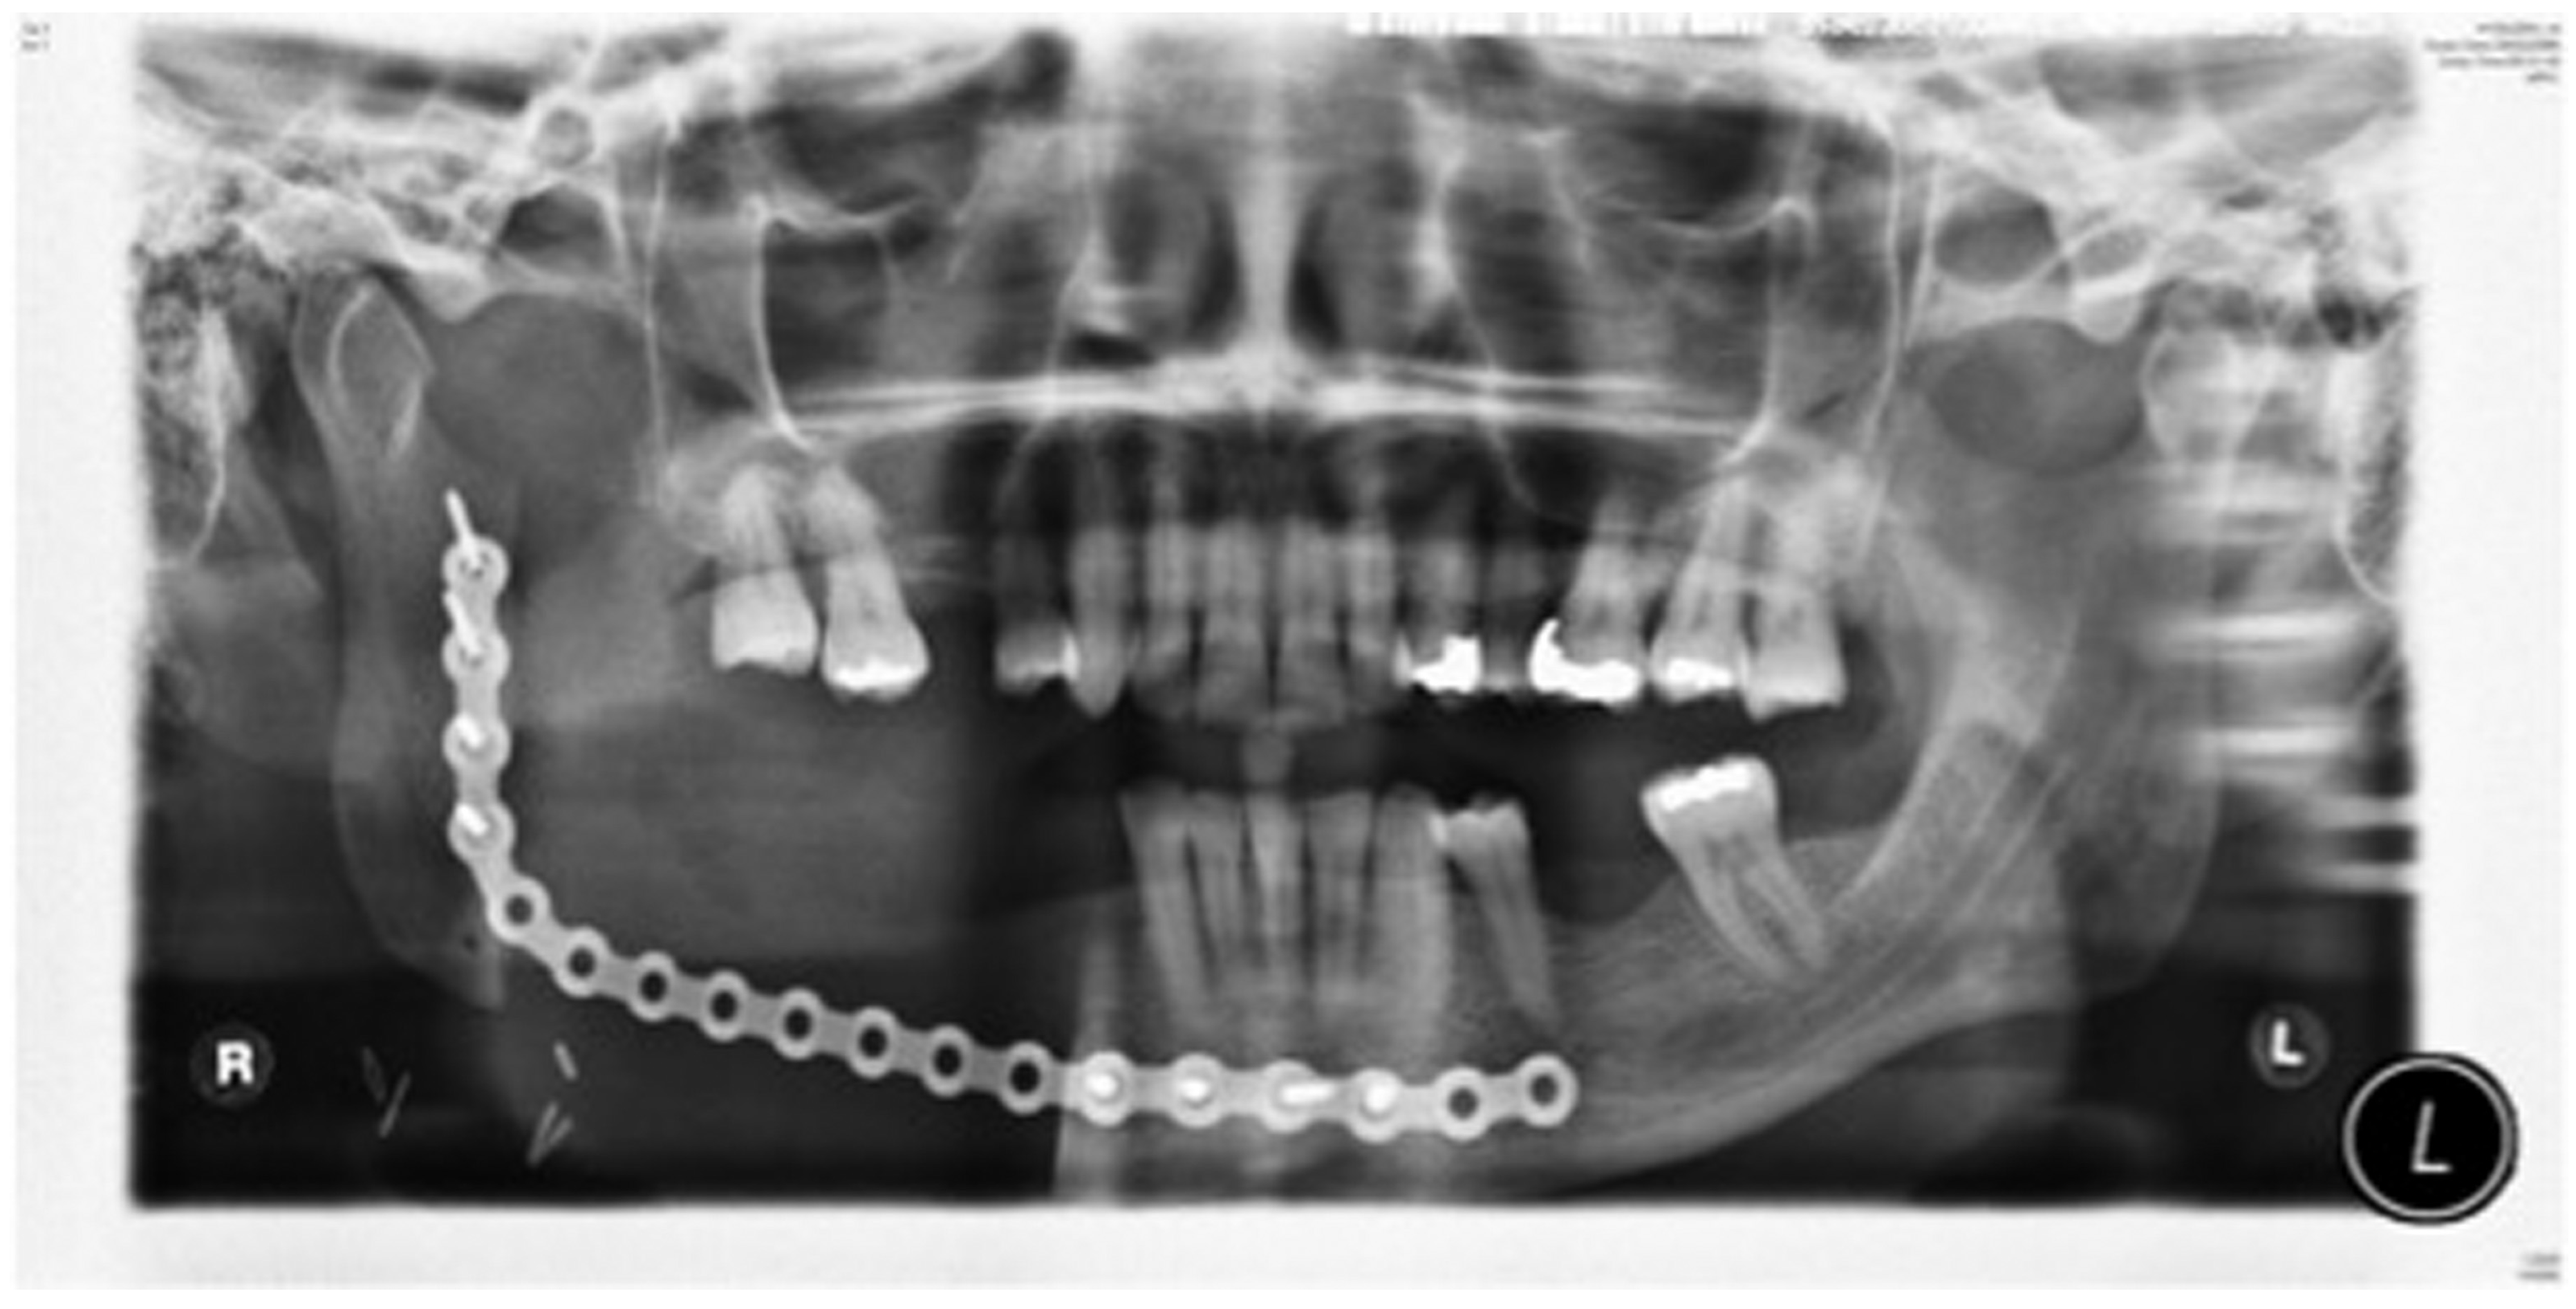

Figure 11.

Orthopantomography(OPT) showing free bone graft placed in segmental defect.

Staged reconstruction was defined as when the reconstruction with the free bone graft was performed as a secondary procedure. This secondary procedure was only performed when the oral mucosa had healed intraorally, sealing the mouth from the defect and the neck. A loadbearing locking mandibular plate was used to maintain the three-dimensional position of the bone and thus the occlusion (see Figure 1, Figure 2, Figure 3, Figure 4, Figure 5, Figure 6, Figure 7, Figure 8, Figure 9, Figure 10 and Figure 11).